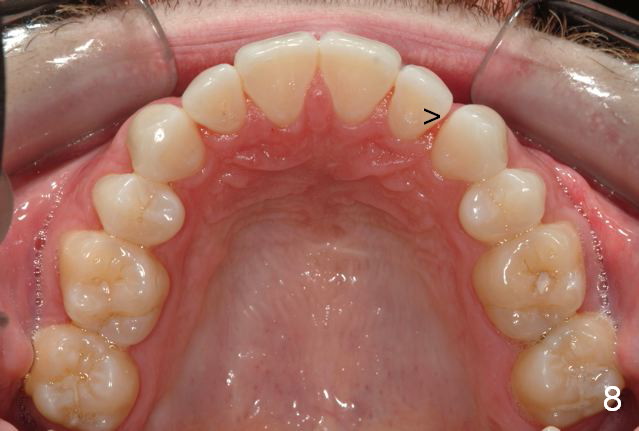

Final photos are taken on 03/23/2016. Mid face deficiency improved, now just a hint (Fig.3). Before (Fig.4,10) and after (Fig.5-9) occlusal adjustment of the canines.